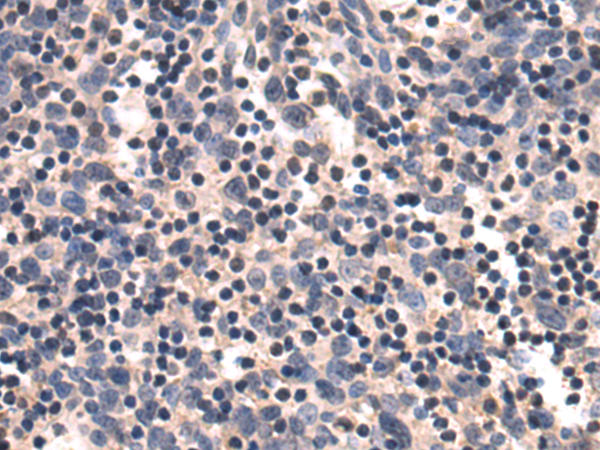

分类: 科研抗体货号: P10703别名: ARO; ARO1; CPV1; CYAR; CYP19; CYPXIX; P-450AROM应用: IHC反应种属: Human, Mouse, Rat